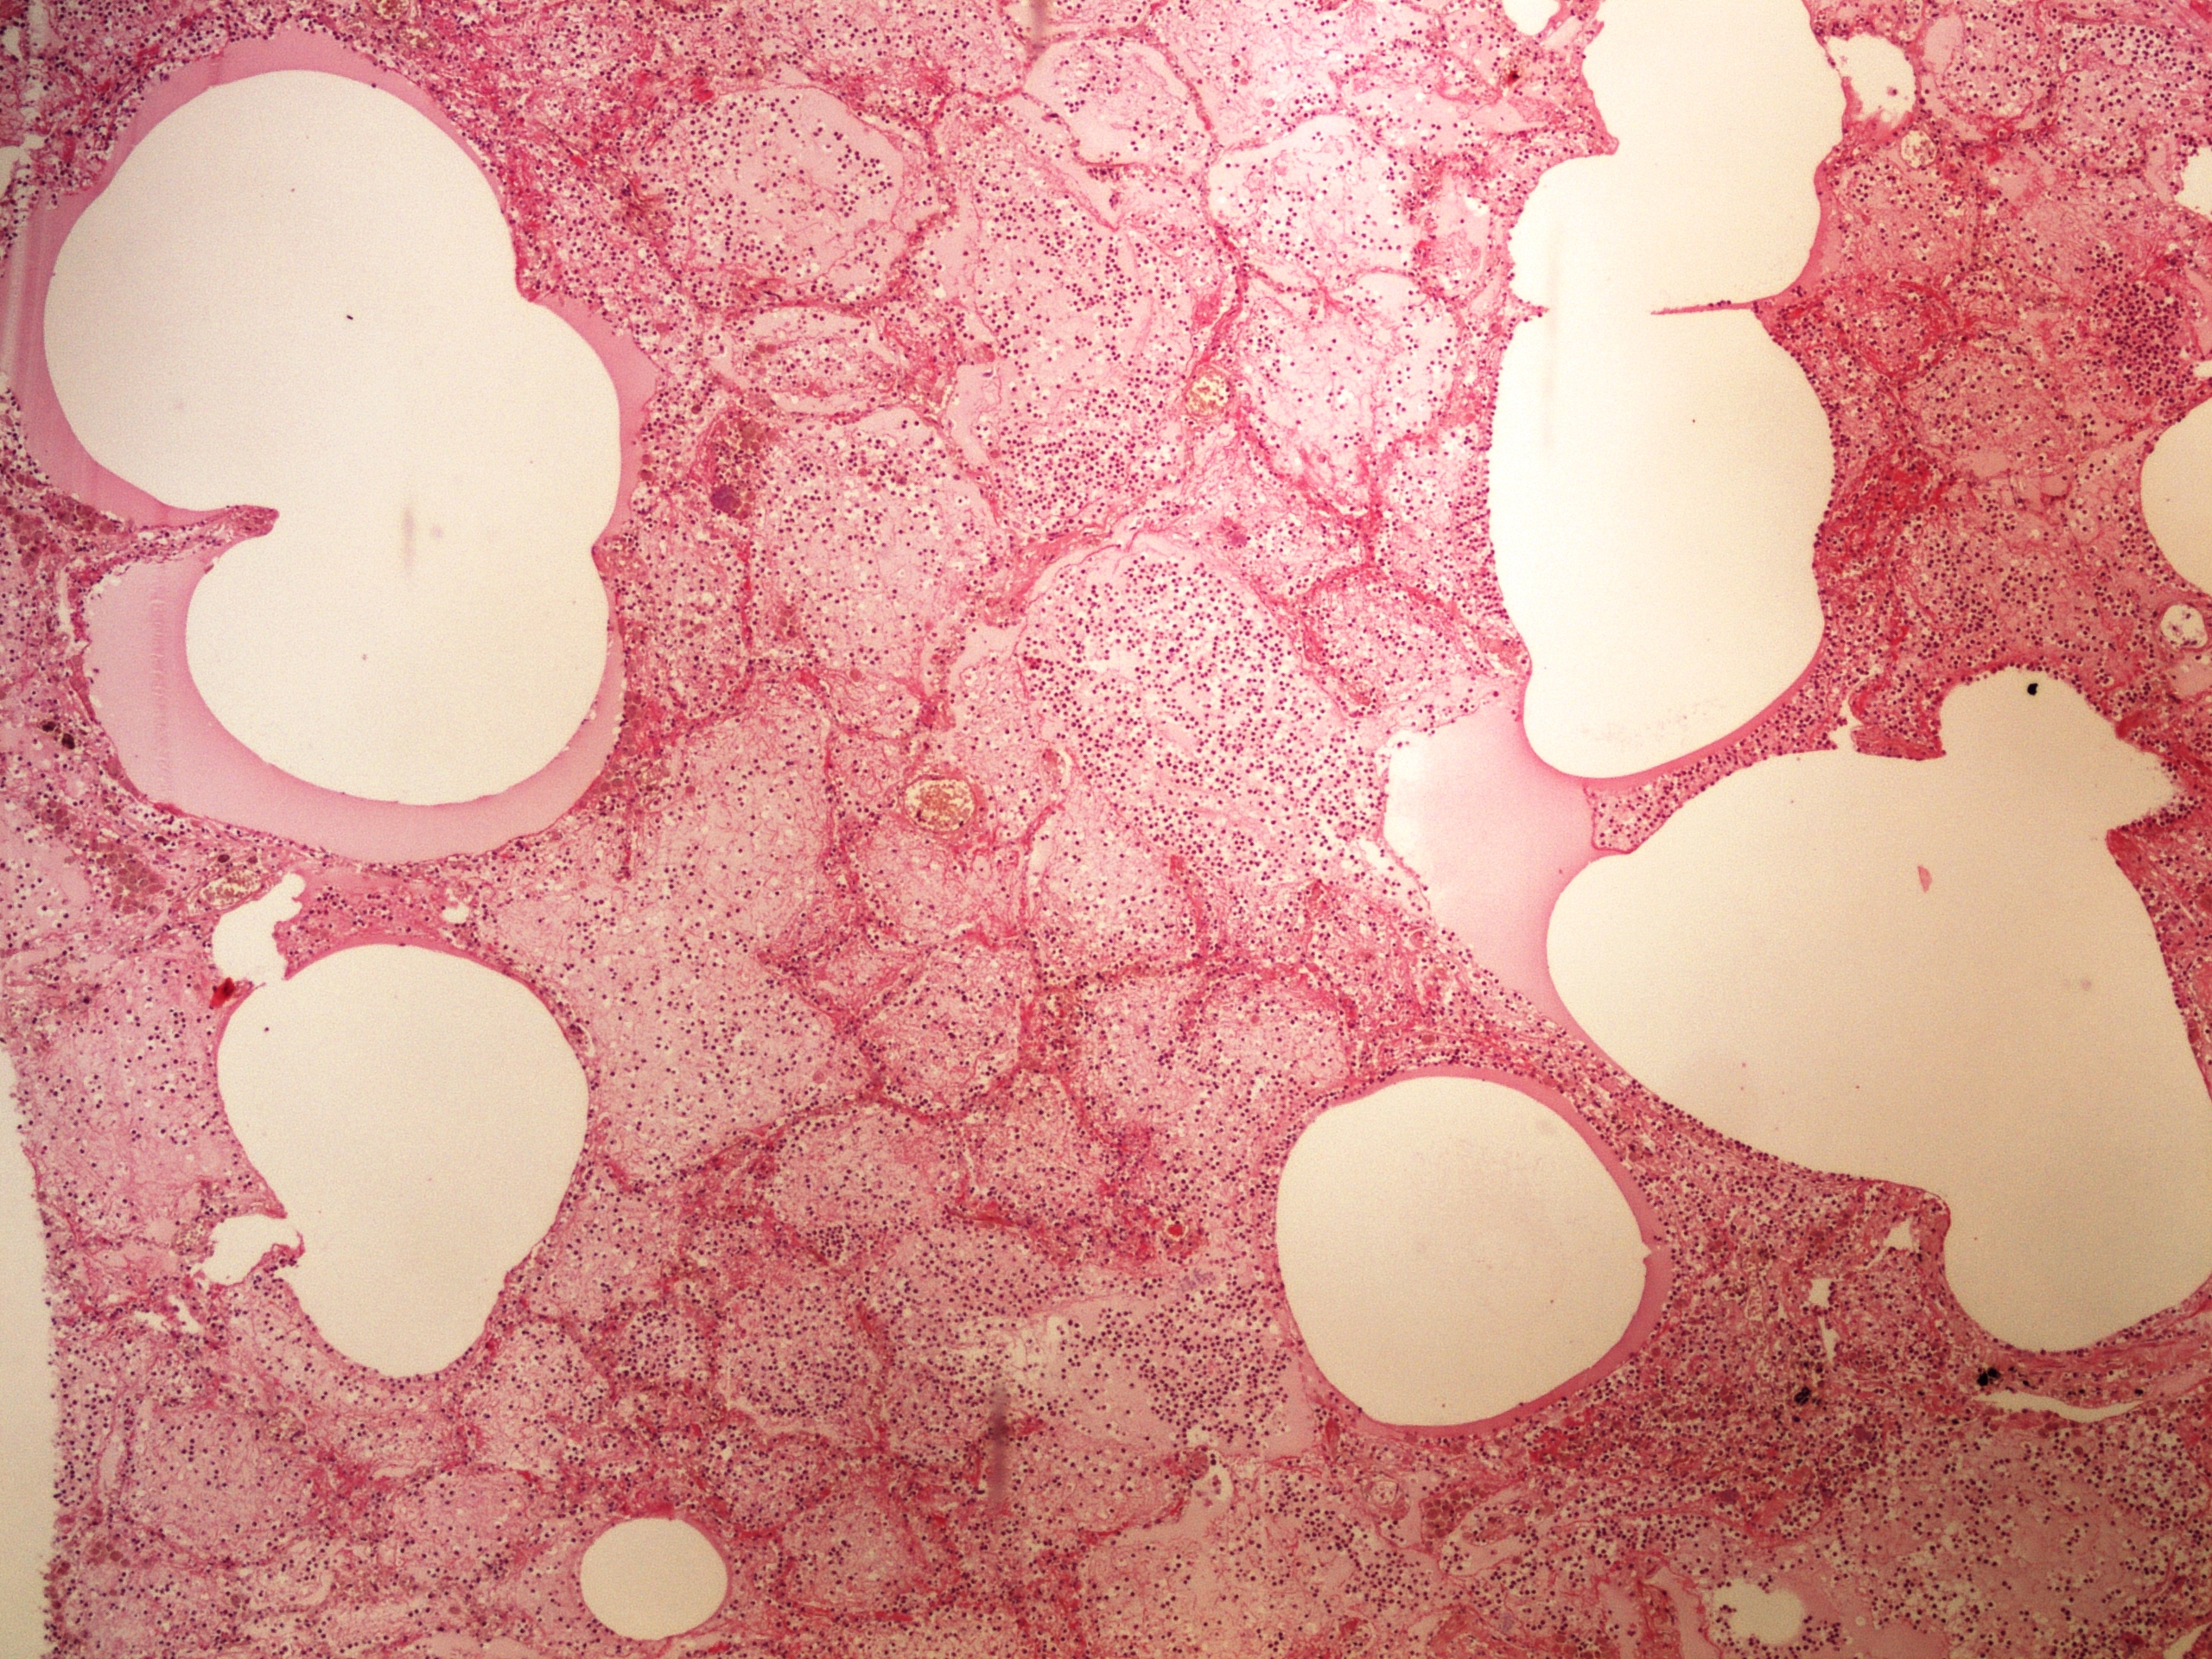

Preparát č.25 a č.26 - miliární TBC jater

Struktury

- miliární uzlík

- vícejaderné buňky Langhansova typu